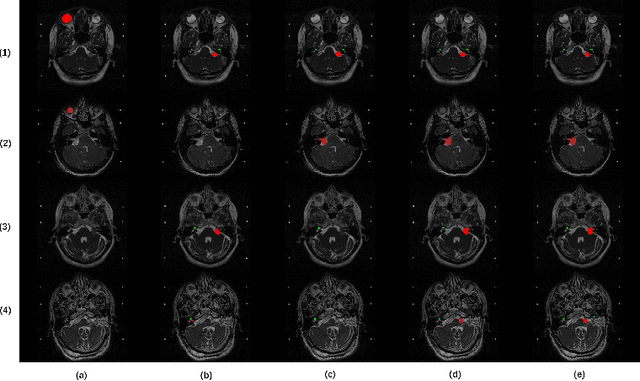

This paper proposes an unsupervised cross-modality domain adaptation approach based on pixel alignment and self-training. Pixel alignment transfers ceT1 scans to hrT2 modality, helping to reduce domain shift in the training segmentation model. Self-training adapts the decision boundary of the segmentation network to fit the distribution of hrT2 scans. Experiment results show that PAST has outperformed the non-UDA baseline significantly, and it received rank-2 on CrossMoDA validation phase Leaderboard with a mean Dice score of 0.8395.